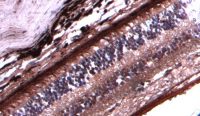

IHC-P analysis of human esophageal tissue using GTX03261 CD168 / RHAMM antibody [GT1346].

Dilution : 1:100